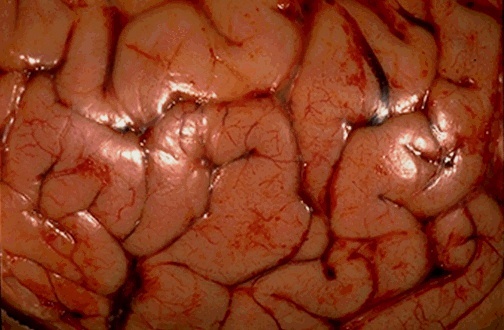

Bacterial meningitis - neutrophilic exudate